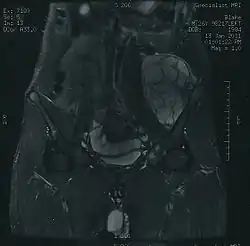

- chrzęstniakomięsak powierzchowny (chondrosarcoma periphericum) – wyrasta z powierzchni kości w obręb otaczających tkanek, najczęściej zajmując kości miednicy i proksymalną część kości udowej; zazwyczaj rośnie powoli

- chrzęstniakomięsak mezenchymalny (chondrosarcoma mesenchymale) – zwykle rozwija się w kościach twarzy i miednicy; przebieg jest niekorzystny

- chrzęstniakomięsak odróżnicowany (chondrosarcoma dedifferentiatum) – z reguły rozwija się w kościach miednicy, kości udowej i ramiennej; przebieg też jest niekorzystny, 90% chorych umiera do 2 lat po zakończeniu leczenia